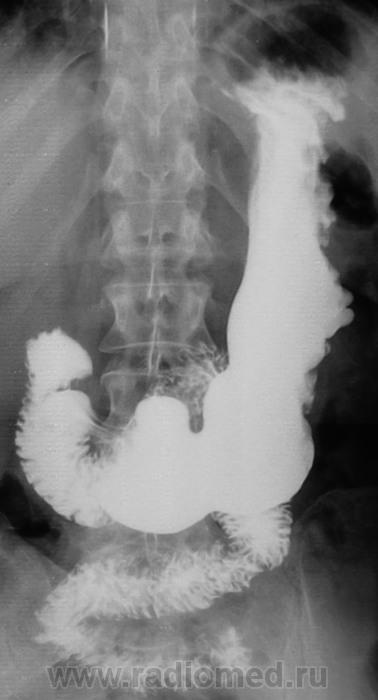

Пол пациента: Женский пол Тип патологии: Другое Область исследования: Пищеварительная система Методы исследования: Rg Один снимок желудка. Может быть мнения будут? https://radiomed.ru/sites/default/files/styles/case_slider_image/public/user/12/2.201201010012.jpg?itok=f3YpbTf6 https://radiomed.ru/sites/default/files/styles/case_slider_image/public/user/12/3.201201010013.jpg?itok=DZdw77nQ https://radiomed.ru/sites/default/files/styles/case_slider_image/public/user/12/4.201311120014.jpg?itok=z9RZUMmQ ID:33225 Ср, 13/11/2013 - 22:10 #1 Дмитрий Волегов Не на сайте Был на сайте: 3 года 6 месяцев назад Зарегистрирован: 22.05.2013 - 00:32 Публикации: 1148 Варикозные вены? С Уважением, Дмитрий. Ср, 13/11/2013 - 22:11 #2 vadim losevichev Не на сайте Был на сайте: 7 лет 2 месяцев назад Зарегистрирован: 27.01.2013 - 09:45 Публикации: 679 Большая кривизна у тела желудка странная. Non progrĕdi est regrĕdi. Ср, 13/11/2013 - 22:11 #3 Катенёв Валенти... Не на сайте Был на сайте: 7 лет 4 недели назад Зарегистрирован: 22.03.2008 - 22:15 Публикации: 54876 Дмитрий Волегов wrote: Варикозные вены? Это стопудово, или дифряд? Ср, 13/11/2013 - 22:25 #4 Дмитрий Волегов Не на сайте Был на сайте: 3 года 6 месяцев назад Зарегистрирован: 22.05.2013 - 00:32 Публикации: 1148 Катенёв Валентин Львович wrote: Дмитрий Волегов wrote: Варикозные вены? Это стопудово, или дифряд? На мой взгляд скиалогия характерная, но опыта мало. В дифряд. С Уважением, Дмитрий. Ср, 13/11/2013 - 22:26 #5 Катенёв Валенти... Не на сайте Был на сайте: 7 лет 4 недели назад Зарегистрирован: 22.03.2008 - 22:15 Публикации: 54876 vadim losevichev wrote: Большая кривизна у тела желудка странная. Да, для нормы странноватая. Ср, 13/11/2013 - 22:32 #6 алкс Не на сайте Был на сайте: 10 лет 4 недели назад Зарегистрирован: 24.10.2012 - 22:55 Публикации: 2915 Лежа бы вниз головой... Ну а так, дефект наполнения по большой кривизне свода. М.б. что угодно, больше за гиперплазию или онко. Ср, 13/11/2013 - 22:37 #7 Катенёв Валенти... Не на сайте Был на сайте: 7 лет 4 недели назад Зарегистрирован: 22.03.2008 - 22:15 Публикации: 54876 алкс wrote: Лежа бы вниз головой... Ну а так, дефект наполнения по большой кривизне свода. М.б. что угодно, больше за гиперплазию или онко. Что угодно быть не может. Протокол писать надо, да и заключение... Ср, 13/11/2013 - 22:37 #8 Катенёв Валенти... Не на сайте Был на сайте: 7 лет 4 недели назад Зарегистрирован: 22.03.2008 - 22:15 Публикации: 54876 алкс wrote: Лежа бы вниз головой... Что даст вниз головой? Это положение Тренделенбурга, или как? Ср, 13/11/2013 - 22:43 #9 алкс Не на сайте Был на сайте: 10 лет 4 недели назад Зарегистрирован: 24.10.2012 - 22:55 Публикации: 2915 Катенёв Валентин Львович wrote: алкс wrote: Лежа бы вниз головой... Что даст вниз головой? Это положение Тренделенбурга, или как? Тугое заполнение свода + можно пасс. рефлюкс, или не там патологию вижу? Просто стол опустить с пациентом ( который стоя стоит) на 10-15градусов без вычурных. Ср, 13/11/2013 - 23:03 #10 stovbav Не на сайте Был на сайте: 2 года 2 месяцев назад Зарегистрирован: 20.12.2009 - 17:28 Публикации: 7066 Почему не локальная форма Менетрие?.... Болезни ног: виды, симптомы, причины, профилактика и лечение Ср, 13/11/2013 - 23:16 #11 алкс Не на сайте Был на сайте: 10 лет 4 недели назад Зарегистрирован: 24.10.2012 - 22:55 Публикации: 2915 stovbav wrote: Почему не локальная форма Менетрие?.... Вполне, не я так написал - "гиперплазия" Ср, 13/11/2013 - 23:20 #12 Катенёв Валенти... Не на сайте Был на сайте: 7 лет 4 недели назад Зарегистрирован: 22.03.2008 - 22:15 Публикации: 54876 stovbav wrote: Почему не локальная форма Менетрие?.... Здравствуйте Виктор Григорьевич! Почему "почему"? "Картинка" то типичная, именно, для болезни Менетрие. Ср, 13/11/2013 - 23:44 #13 stovbav Не на сайте Был на сайте: 2 года 2 месяцев назад Зарегистрирован: 20.12.2009 - 17:28 Публикации: 7066 Катенёв Валентин Львович wrote: stovbav wrote: Почему не локальная форма Менетрие?.... Здравствуйте Виктор Григорьевич! Почему "почему"? "Картинка" то типичная, именно, для болезни Менетрие. Так вопрос то был - риторический))), уважаемый Валентин Львович! Болезни ног: виды, симптомы, причины, профилактика и лечение Чт, 14/11/2013 - 07:53 #14 Андрей Юрьевич Не на сайте Был на сайте: 2 недели 1 день назад Зарегистрирован: 16.11.2008 - 22:16 Публикации: 18098 Менетрие? По одному снимку, без второй порции бария, без шипучки и снимков в горизонтальном положении. Как-то лихо. Андрей Юрьевич Чт, 14/11/2013 - 12:39 #15 stovbav Не на сайте Был на сайте: 2 года 2 месяцев назад Зарегистрирован: 20.12.2009 - 17:28 Публикации: 7066 Андрей Юрьевич wrote: Менетрие? По одному снимку, без второй порции бария, без шипучки и снимков в горизонтальном положении. Как-то лихо. Все это так...но ответ то по ОДНОМУ снимку надо дать...так что - имеем, что имеем: один снимок - и ряд мнений)))) Болезни ног: виды, симптомы, причины, профилактика и лечение Чт, 14/11/2013 - 20:47 #16 И.Бондаренко Не на сайте Был на сайте: 1 день 3 часа назад Зарегистрирован: 13.09.2011 - 22:55 Публикации: 9206 На вашем аппарате тубус (компрессия) есть? Чт, 14/11/2013 - 23:50 #17 Катенёв Валенти... Не на сайте Был на сайте: 7 лет 4 недели назад Зарегистрирован: 22.03.2008 - 22:15 Публикации: 54876 Андрей Юрьевич wrote: Менетрие? По одному снимку, без второй порции бария, без шипучки и снимков в горизонтальном положении. Как-то лихо. Вы правы! Снимок не один, выставлен один для "мозгового штурма". Пациент наблюдается уже в течение пяти лет, консультирован, обследовался и лечился в ОКБ. Чт, 14/11/2013 - 23:52 #18 Катенёв Валенти... Не на сайте Был на сайте: 7 лет 4 недели назад Зарегистрирован: 22.03.2008 - 22:15 Публикации: 54876 И.Бондаренко wrote: На вашем аппарате тубус (компрессия) есть? У нас имеется все. Компрессия не только тубусом и но мягкими "валиками". Пояснения в предыдущем посте. Пт, 15/11/2013 - 00:17 #19 Dima Не на сайте Был на сайте: 7 лет 2 месяцев назад Зарегистрирован: 05.08.2012 - 17:39 Публикации: 2467 Спасибо за интересное наблюдение, Валентин Львович! Если есть возможность покажите пожалуйста все рентгенограммы выполненные в процессе исследования. Терпимость - это когда прощают чужие ошибки; такт - когда не замечают их. (Артур Шницлер)

Варикозные вены?

Большая кривизна у тела желудка странная.

Лежа бы вниз головой... Ну а так, дефект наполнения по большой кривизне свода. М.б. что угодно, больше за гиперплазию или онко.

Почему не локальная форма Менетрие?....

"Картинка" то типичная, именно, для болезни Менетрие.

Менетрие? По одному снимку, без второй порции бария, без шипучки и снимков в горизонтальном положении. Как-то лихо.

Снимок не один, выставлен один для "мозгового штурма".

Пациент наблюдается уже в течение пяти лет, консультирован, обследовался и лечился в ОКБ.